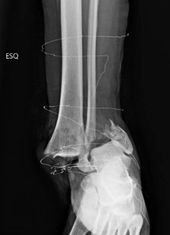

Dislocated Fractures of the Ankle

Compilation of interesting X-rays of Fractures of the ankle with dislocation, multiples types of lesions.